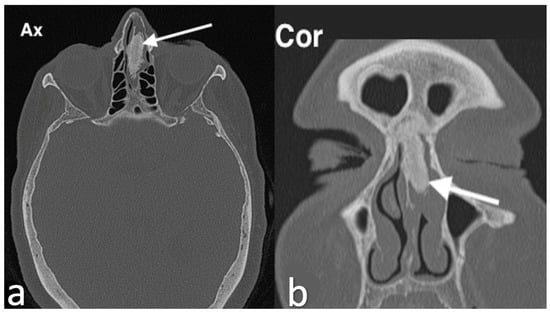

3.2.9. Lipoma

3.2.10. Sinonasal Tract Angiofibroma